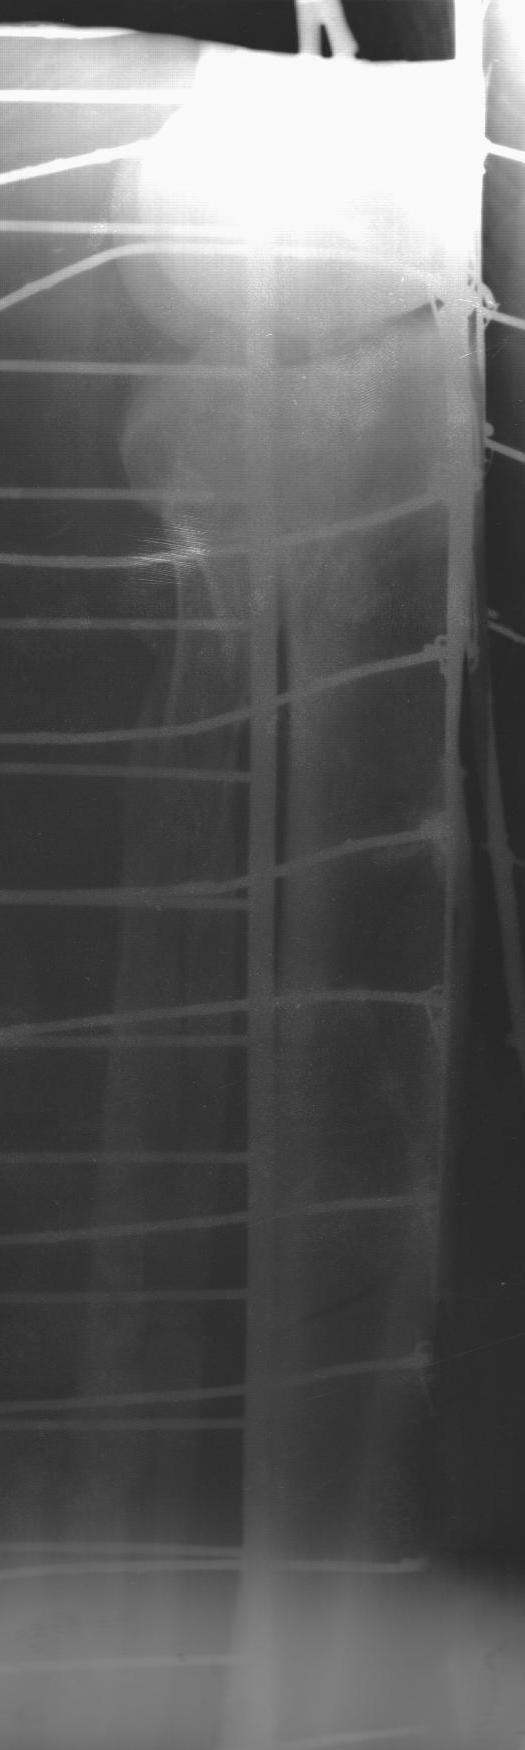

Мужчина 36 л, травму получил 13.12.2010 при падении с высоты (около 2 м), травма изолированная - оскольчатый перелом латерального мыщелка и в/з-с/з диафиза большеберцовой кости. Доставлен в ЛПУ через 30 мин, при поступлении наложено скелетное вытяжение за пяточную кость. На 2-3-и сутки развился выраженный отек в/з-с/з голени, появились сильные боли в голени, парестезии в стопе (компартмент с-м?), консервативно купированы. На данный момент сохраняется выраженный отек голени, боли умеренные, движения в стопе сохранены, пульсация артерии тыла стопы сохранена.

Интересует срок проведения оперативного вмешательства, оптимальный выбор фиксатора (особенно интересует возможность БИОС - мнение А. Н. Челнокова). На месте доступны все основные методы фиксации, ЭОП отсутствует.